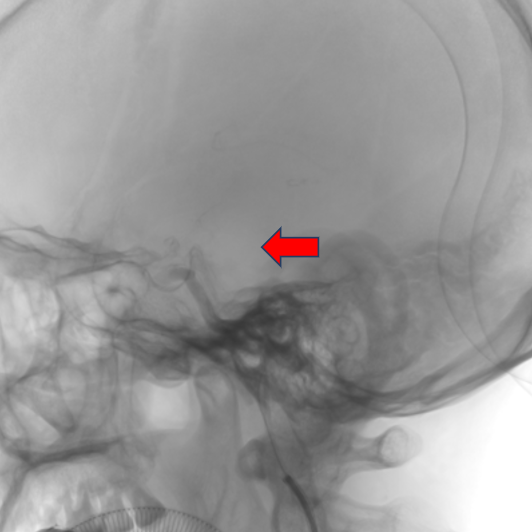

术后第二天影像。

术后1周出院。查体:神志清楚,运动性失语较前明显好转,目前表现为流利程度下降,双侧眼球无凝视,双侧鼻唇沟对称,伸舌居中,双侧肢体肌力5级,肌张力及腱反射正常,双侧病理征未引出。NIHSS评分1分。